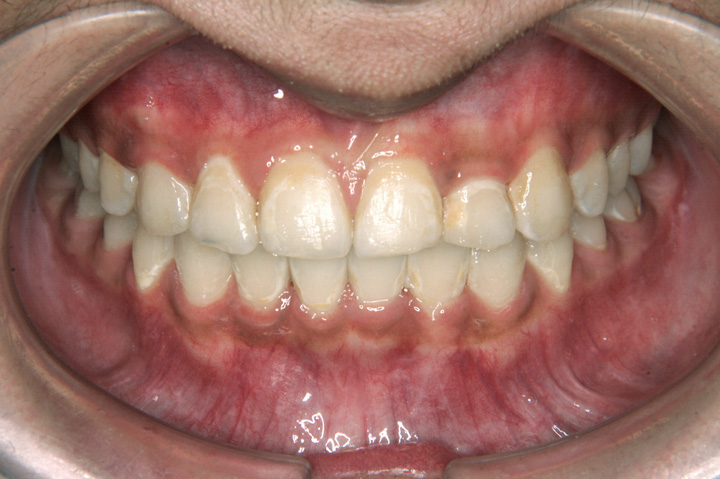

下顎前突(受け口)

叢生(乱ぐい歯)

受け口を主訴に来院された7歳11ヶ月の患者さんです。前歯部反対咬合は機能性の要因もあったため、リンガルアーチとチンキャップを併用し、前歯部のかみ合わせを改善することを優先しました。その後、非抜歯でエッジワイズ装置を用いて配列を行いました。